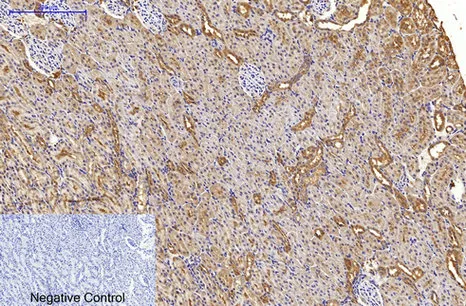

HER2(11H9)Mouse Monoclonal Antibody

Cat: AMM11986

Size1:50μL Price1:$118

Size2:100μL Price2:$220

Size3:200μL Price3:$380

Application:WB,IF-P,IF-F,ICC/IF,IHC-P

Reactivity:Human,Mouse,Rat

Conjugate:Unconjugated

Optional conjugates: Biotin, FITC (free of charge). See other 26 conjugates.

Gene Name:ERBB2